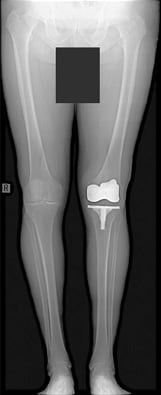

Accurate alignment evaluation

(Both legs for TKA)

(Courtesy of NTT East Corp. Sapporo Hospital, Japan)